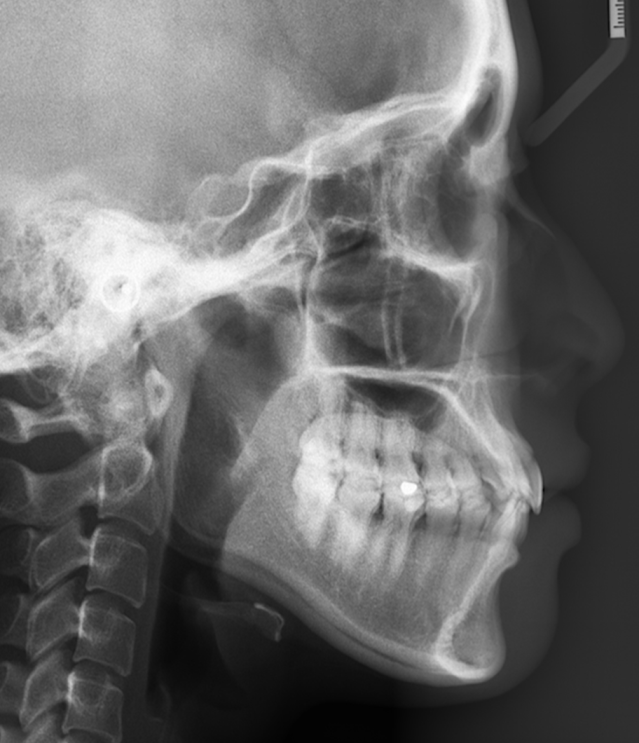

上图这个小姐姐因为牙齿外龅而导致嘴凸,经过20个月的拔牙矫正,牙齿明显内收,侧颜更好看了。

根据医生的测量,可以确定上图这位妹子属于严重的骨性问题,只能通过正畸-正颌联合治疗来改善。最后效果不错哈,矫治前后判若两人。